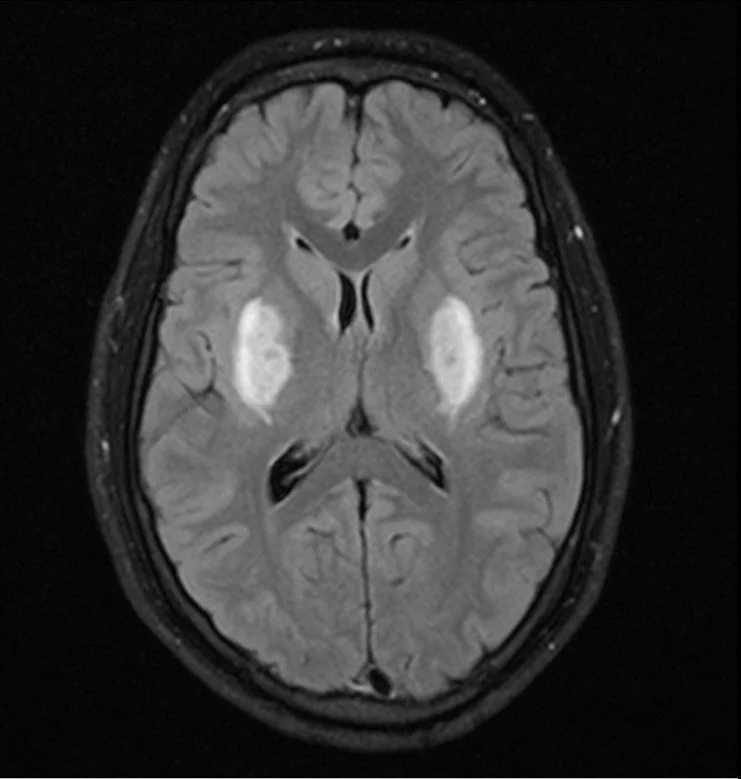

Carbon Monoxide Poisoning

• Classically Symmetric globus pallidus hyperintensity